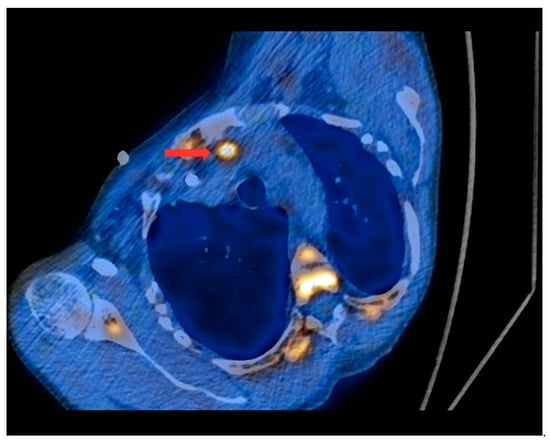

Figure 4.

PET/CT with [11C]MET—axial projection. During the examination, the patient was laid at her left side due to the forced body position caused by numerous fractures and a brown tumor infiltrating the spinal canal (as a result of tHPT). Visible focus of increased radiotracer uptake (red arrow) in the lesion corresponding to the ectopic parathyroid gland, located in the left superior mediastinum retrosternally, and anteriorly from the initial segment of the aortic arch.